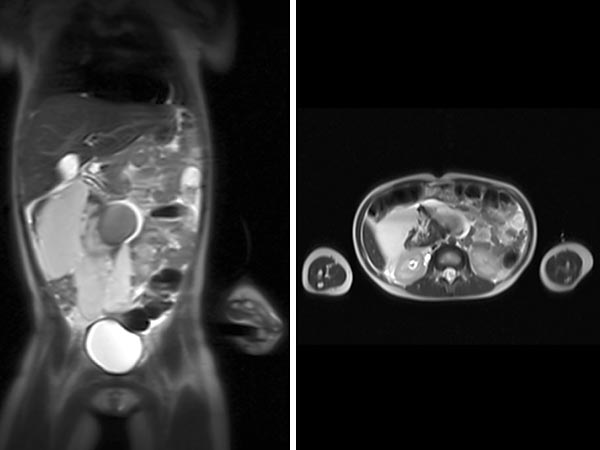

Erster Fall eines 5 Jahre alten Mädchens mit aufgetriebenem Abdomen. Im koronaren und transversalen T2-gewichteten, fettunterdrückten MRT ausgedehnte LM mit großen Zysten, die den Darm verdrängen.